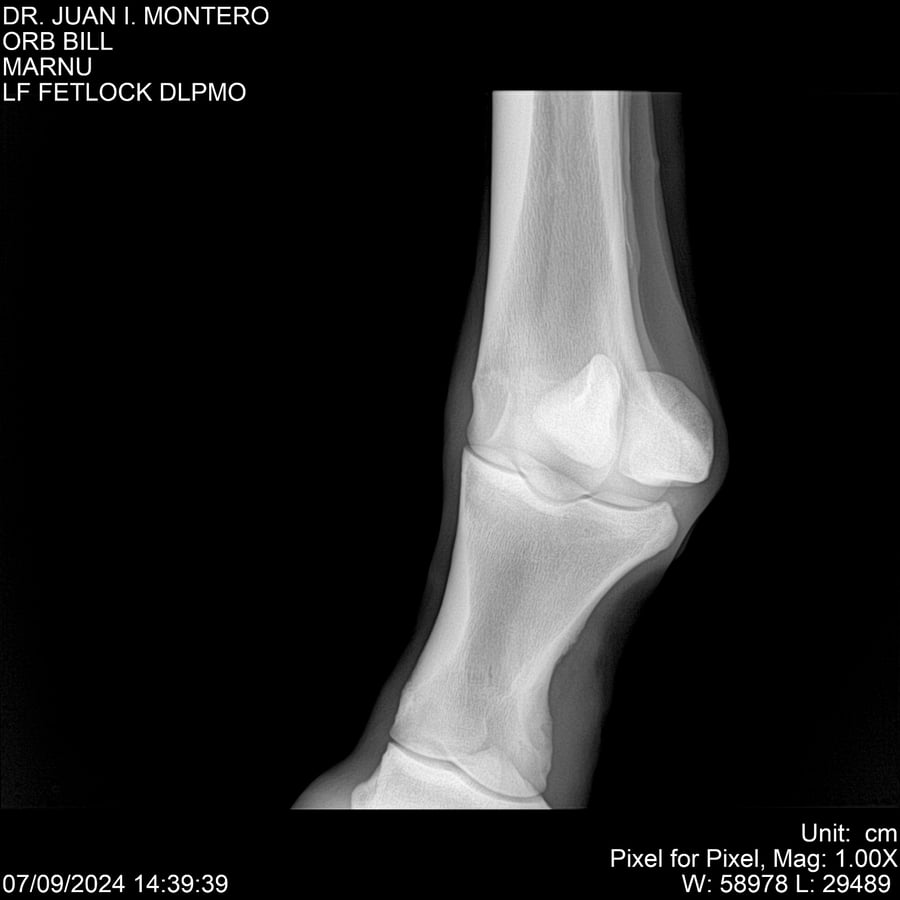

LOTE 7, ORB BILL 🔥 🔥 🔥 Lote Anterior Volver al remate Lote Siguiente Ficha Contacto Montevideo - Ficha del Lote Identificador: #282523 Categoría: Yeguarizos Montevideo - 83 Visualizaciones ClicData Contacto Empresa: Abelenda N. R., Walter Hugo Nombre*: Teléfono* : E-mail* : Mensaje Enviar Registrese gratis Este contenido Exclusivo está disponible sólo para usuarios registrados Ingresar